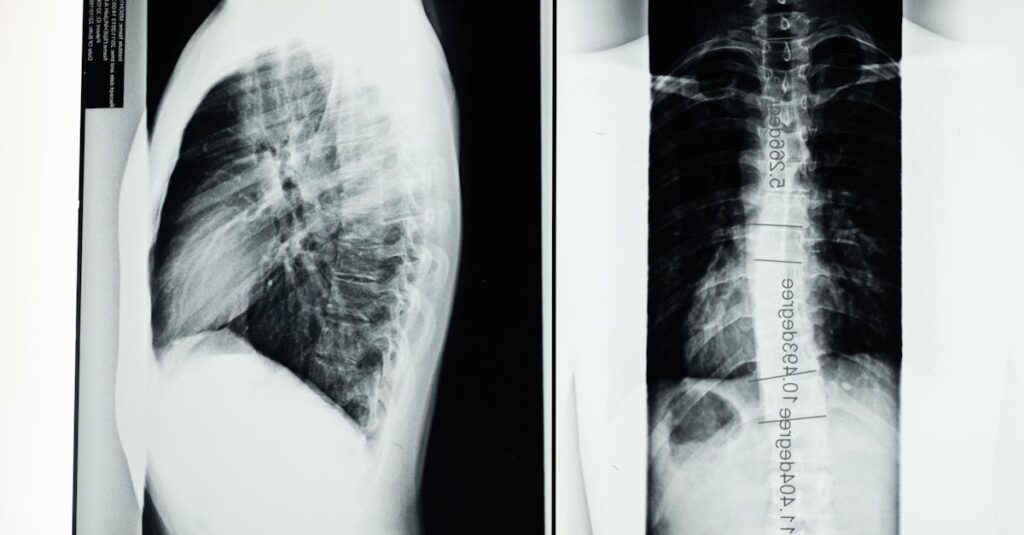

Quels examens sont nécessaires avant de commencer un traitement de décompression pour un disque écrasé?

Une IRM ou une radiographie est souvent recommandée pour évaluer l’état de la colonne vertébrale.

Quels examens permettent de diagnostiquer un pincement discal?

Une IRM ou une radiographie est souvent utilisée pour confirmer le diagnostic d’un pincement discal ou d’un disque écrasé.